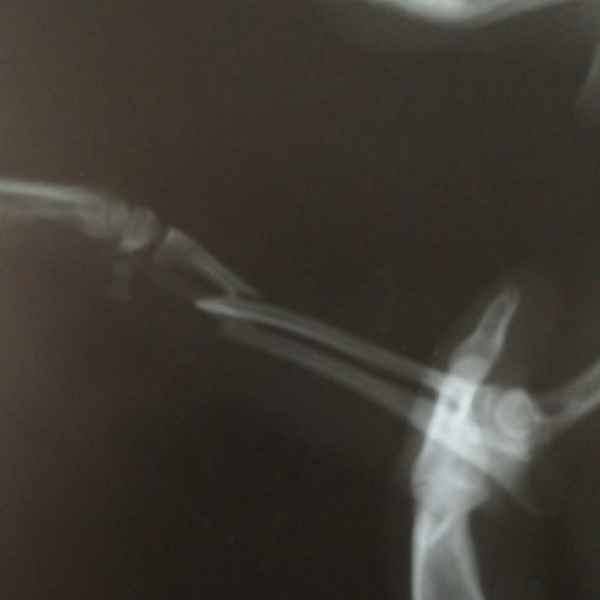

Этот пациент поступил к нам с кусаной раной левой грудной конечности После рентгенологического исследования обнаружили перелом костей предплечья. Сложность операции заключалось в том, что дистальный отросток лучевой кости был очень коротким. Хирургом нашей клиники было принято решение установить блокируемую lcp пластину. В данный момент пациент полностью восстановился..

Этот пациент поступил к нам после падения с 14 этажа. На основании комплекса исследований ,была установлена полиорганная недостаточность, перелом головки бедренной кости и трех пястных костей. Прием причинял сильную боль ,ведь был перелом нижней челюсти. Нами было принято решение по установке эгофагостомы. Ежедневно проводилась инфузионная терапия и только после полной стабилизации животного была проведена хирургическая операция по восстановлению костей.